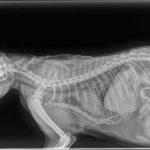

A vérképzése gyakorlatilag leállt, alig termel vörös vérsejtet a szervezete, súlyosan vérszegény. A teljes test röntgen nem mutatott ki súlyos elváltozást, egy légpuska lövedéket találtak a füle mögött.